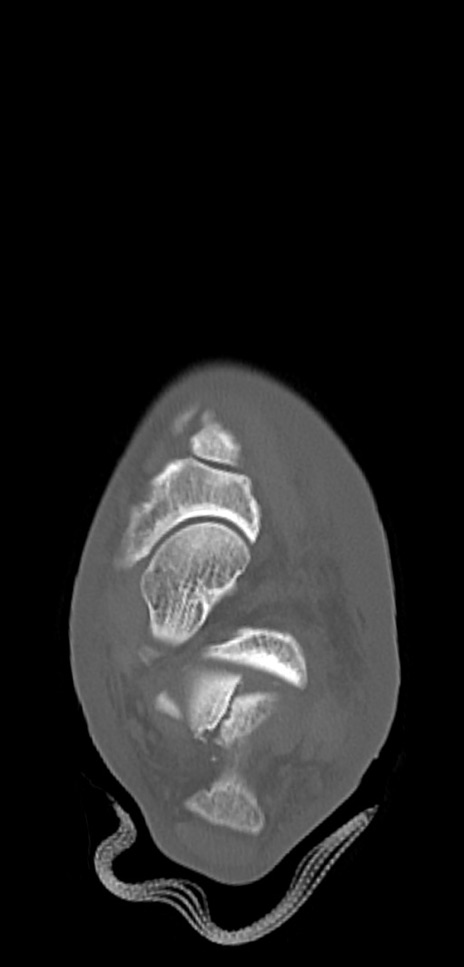

症例37 左足関節CT(横断像)

左足関節CT